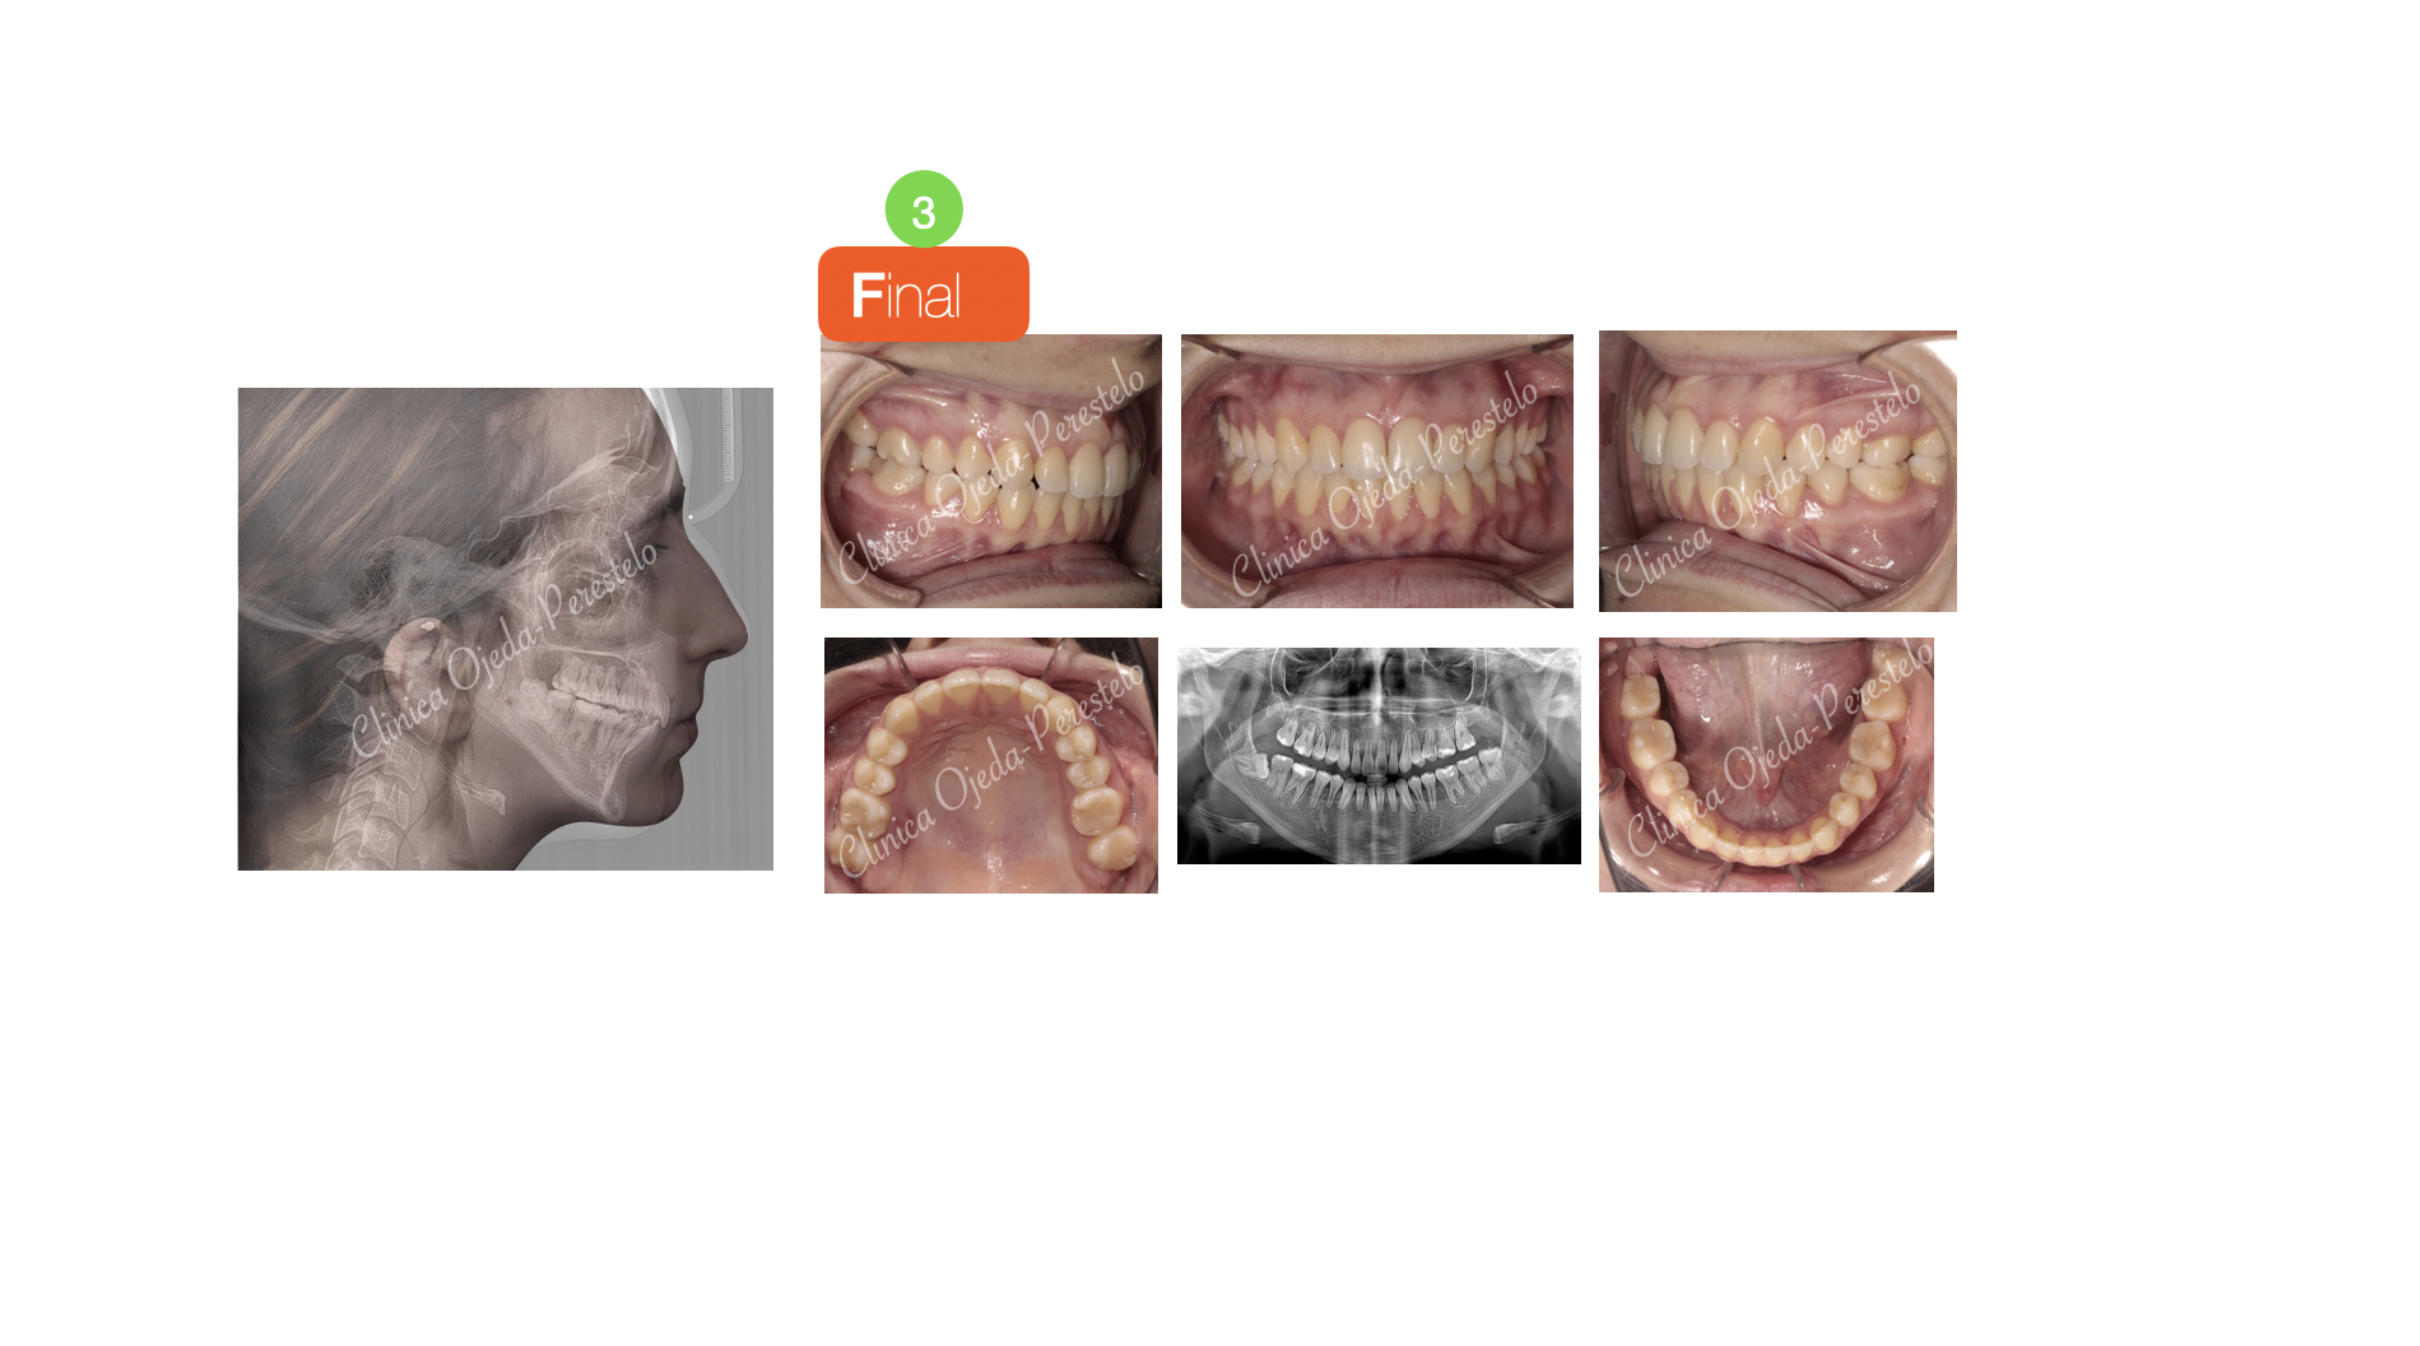

Paciente con problemas masticatorios tratada con Disyunción Oseosoportada (MARPE) y con Microtornillos (2) para el cierre de la Mordida Abierta. Se han alineado y nivelado ambas arcadas con brackets de autoligado pasivo (Sistema Damon) y elásticos intermaxilares.

Quisieramos destacar la amplitud en la sonrisa alcanzada y el gran cierre en la mordida, dotándole a la paciente de una correcta función masticatoria.